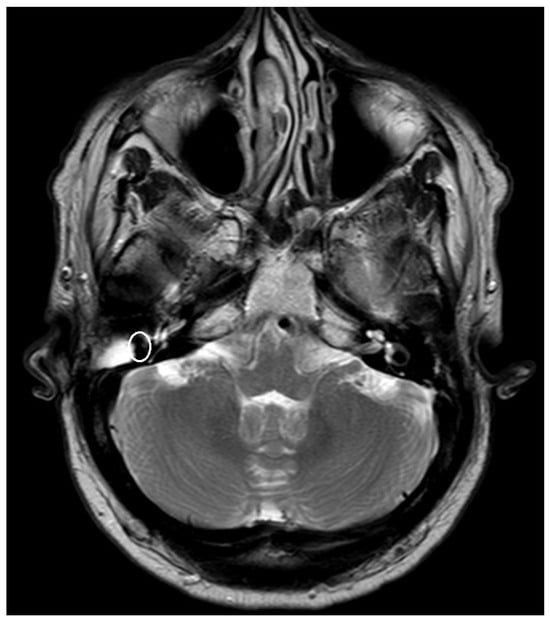

| PORP | 2.0 mm | 3.1 mm | 5.4 mm |

| TORP | 3.6 mm | 4.7 mm | 7.2 mm |

| Mesh | 0.1 mm | 3.6 mm | 5.8 mm |